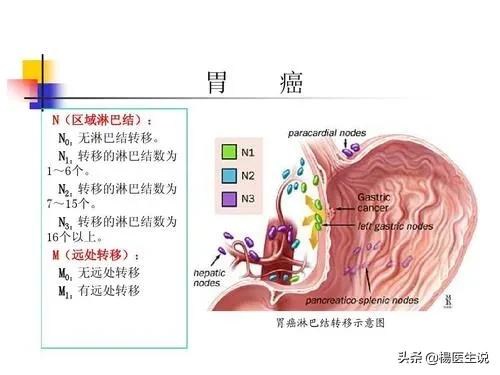

胃がんにつながる可能性のある病気:

- 萎縮性胃炎

- 残留性胃炎

- 消化性潰瘍

- メネトリエ病

- ヘリコバクター・ピロリ感染を合併した胃炎

- 胃ポリープと胃腺腫

- 腸上皮過形成または異形成を伴う慢性胃炎

1.慢性萎縮性胃炎:慢性萎縮性胃炎は前癌病変と呼ばれ、中等度、重度の萎縮性胃炎は重度の異型粘膜過形成に発展する可能性があり、悪い食習慣に刺激されると胃癌に発展する可能性がある。従って、重度の萎縮性胃炎が発生した場合、あるいは異型過形成が発生した場合は、この時期により警戒する必要があり、対応する薬物介入に加えて、3~6ヶ月ごとに胃カメラ検査と腫瘍マーカーなどの関連検査を受け、揺籃期に前癌病変を死滅させる必要がある。

- 慢性萎縮性胃炎と胃潰瘍は胃癌の前癌病変である。この2つの病気には共通の原因があり、ヘリコバクター・ピロリという名前の小さな小さな細菌である。

ピロリ菌の最も一般的な診断方法は、「泡を吹く」検査、すなわちC13およびC14呼気検査であり、簡単で便利、苦痛がなく、精度が高い。最も一般的な診断方法は "泡を吹く "検査、すなわちC13とC14の呼気検査で、簡単で便利、痛みもなく正確です。 4剤併用療法は、1種類の酸抑制剤+2種類の抗生物質+1種類のビスマスである。胃がんの早期発見には定期的な胃カメラが不可欠。